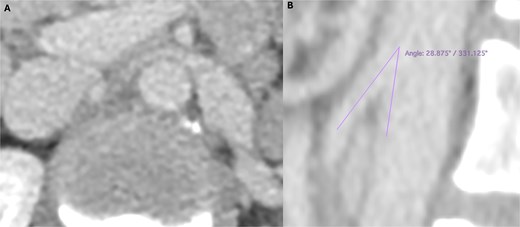

Lab tests showed microscopic haematuria (>0.45 × 106/l). Doppler ultrasound revealed LRV compression, with a diameter reduction from 12.5 to 1.5 mm, and a peak systolic velocity increase from 34 to 160 cm/s (velocity ratio > 4). CT angiography (Fig. 1) confirmed an aortomesenteric angle of 28° and ectasia of the left ovarian vein (9 mm).

Preoperative computed tomography angiography demonstrating compression of the left renal vein in axial section (A) and sagittal section (B), revealing an aortomesenteric angle of 28°.

On CT angiography, the ‘beak sign’ and a diameter ratio ≥ 4.9 between the hilar and aortomesenteric segments are highly specific [6]. An aortomesenteric angle <35° is also supportive. MRI avoids radiation and can reveal LRV compression and gonadal vein varices, though lacks dynamic flow assessment [4]. The gold standard remains venography showing a renocaval gradient ≥3 mmHg, with intravascular ultrasound (IVUS) as a useful adjunct [7].